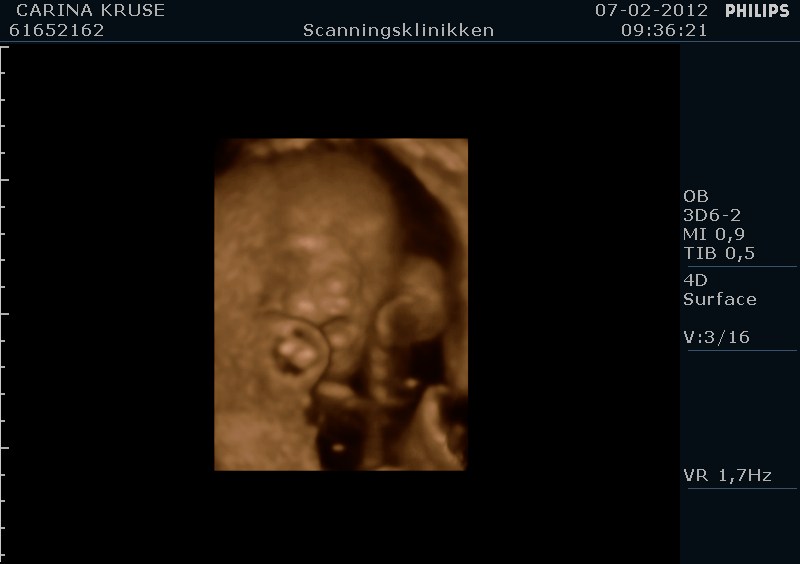

Og sikke en oplevelse, vores lille Filucca lå dog bare og sov som en sten hehe, men vi fik da lige et enkelt gab inden vi sluttede

Her er lige et par billeder af vores lille babypige